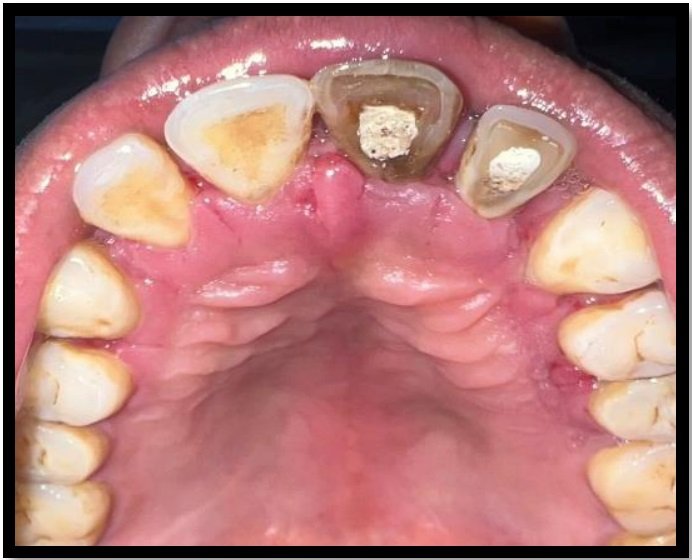

Case 2 illustrations (a) Palatal perforation on tooth 8 (b What Is Palatal Perforation Acquired palatal perforations can be. the vasoconstrictive and caustic effect of the drug can produce direct irritation and ischemia of the nasal and palatine. chronic necrosis destroys the palatal bone to leave a bony sequester which eventually leads to palatal perforation. we present two cases of palatal perforations caused by tertiary syphilis and cocaine abuse respectively. . What Is Palatal Perforation.